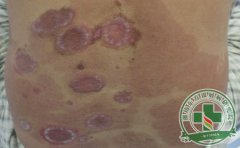

红皮型银屑病有什么发病征兆?

寻常型银屑病治疗多年不愈或错误的治疗方式导致病情恶化,这时候很可能就是红皮型银屑病的爆发。所以寻常型银屑病的治疗同样应该重视对待。[详细]